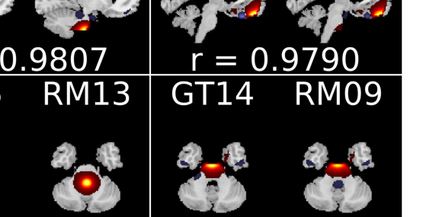

In the last two decades, unsupervised latent variable models---blind source separation (BSS) especially---have enjoyed a strong reputation for the interpretable features they produce. Seldom do these models combine the rich diversity of information available in multiple datasets. Multidatasets, on the other hand, yield joint solutions otherwise unavailable in isolation, with a potential for pivotal insights into complex systems. To take advantage of the complex multidimensional subspace structures that capture underlying modes of shared and unique variability across and within datasets, we present a direct, principled approach to multidataset combination. We design a new method called multidataset independent subspace analysis (MISA) that leverages joint information from multiple heterogeneous datasets in a flexible and synergistic fashion. Methodological innovations exploiting the Kotz distribution for subspace modeling in conjunction with a novel combinatorial optimization for evasion of local minima enable MISA to produce a robust generalization of independent component analysis (ICA), independent vector analysis (IVA), and independent subspace analysis (ISA) in a single unified model. We highlight the utility of MISA for multimodal information fusion, including sample-poor regimes and low signal-to-noise ratio scenarios, promoting novel applications in both unimodal and multimodal brain imaging data.